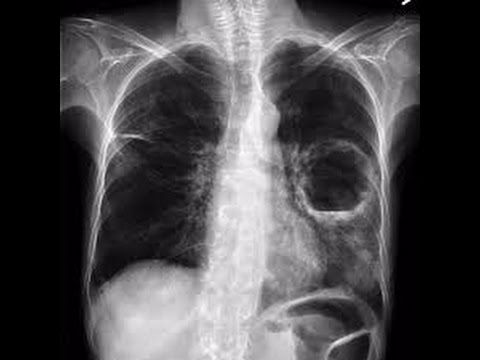

4 จากรูปนี้ ผู้ป่วยรายนี้น่าจะมีภาวะใด

6 จากรูป ผู้ป่วย Pneumonia จะตรวจพบความผิดปกติใด